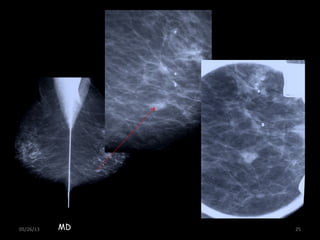

05/26/13 25MD

Magnif. PIEZA QUIRURGICA

• 25.